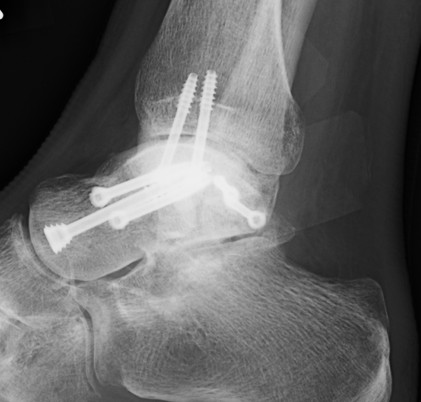

BlairblairAnkle Blair Fusion LateralAnkle Blair Fusion AP